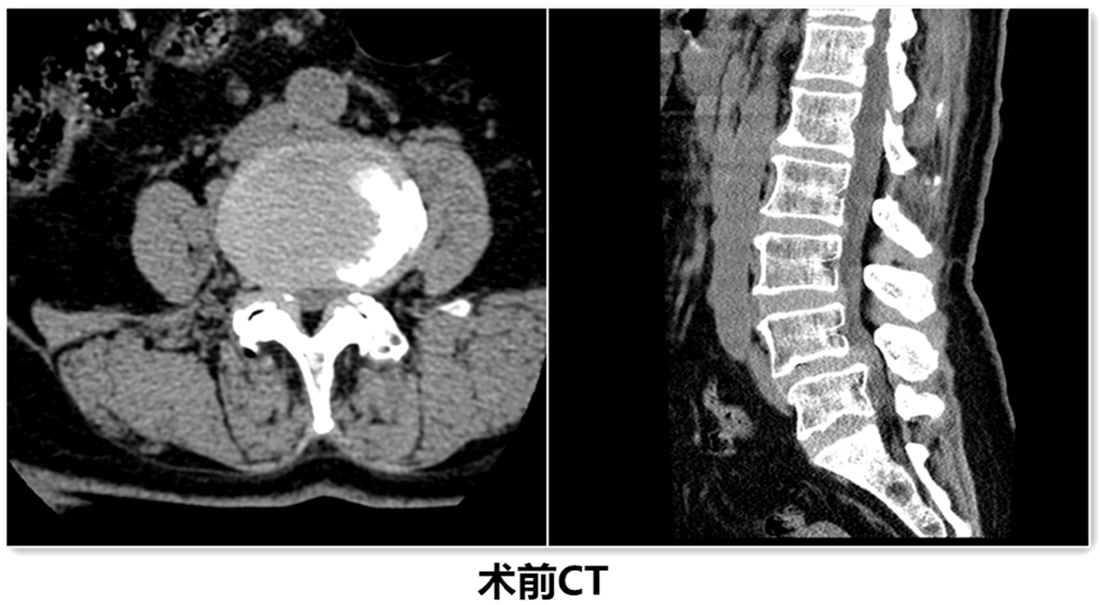

患者郭某,老年女性,因“反复腰部疼痛伴右下肢疼痛、麻木,不能行走”经多家医院诊治效果不好,遂来我院治疗。诊断为腰椎椎管狭窄并腰4/5椎体滑脱,入院后给予仔细查体及辅助检查。

经检查该患者L4椎体退变性滑脱诊断较为明确,且伴有严重的椎管狭窄症状。由腰椎X线动力位片示腰椎不稳,腰椎融合术为最佳治疗方案。结合病人病情、年龄及身体条件,经腰椎间盘治疗中心团队反复论证,认为采取微创镜下融合术为最佳方案。刘维克主任介绍原本需要开放才能完成的手术现在微创下完成,需要攻克2个难点:一是需要在脊柱内镜下给予充分的减压,二是在微创通道下处理椎间盘和终板,并安全的植入融合器。